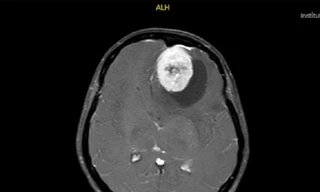

Thực hiện chụp CT, kết quả cho thấy, thanh gỗ dài 30cm đâm thủng thuỳ trên phổi phải và làm đứt một số tĩnh mạch trong nhu mô phổi phải của ông D. Tiến hành hội chẩn, các bác sĩ đã quyết định xử trí phẫu thuật cấp cứu lấy dị vật cho bệnh nhân.

Thám sát vết thương thấy dị vật cắm vào thuỳ trên phổi phải sâu 4cm, đường kính 2x2cm, có tràn máu màng phổi phải lượng trung bình và gãy xương sườn số 4. Ekip mổ đã lấy lấy dị vật, lấy hết máu tụ ra khỏi cơ thể bệnh nhân. Đồng thời, bơm rửa vết mổ, cầm máu, đặt ống dẫn lưu để theo dõi.